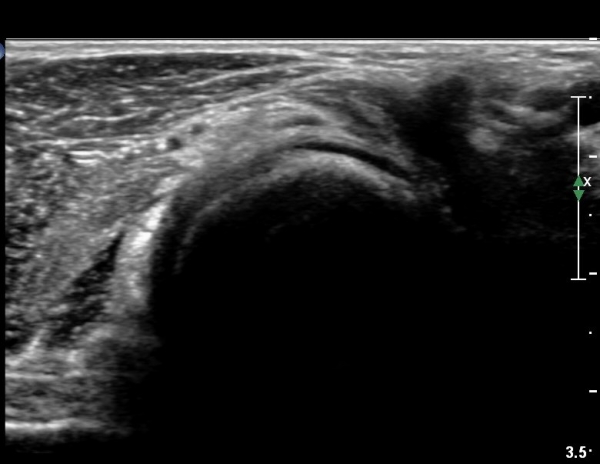

¿Ü»ó°ú¿¡¼­ ¼Õ¸ñ ½ÅÀü°Ç ´ÜµÎ Á¾´Ü¸é°Ë»ç¿¡¼­ ƯÀÌ ¼Ò°ßÀ» º¸ÀÌÁö ¾Ê´Â´Ù(»çÁø 1, 2)

¿ä°ñµÎ ºÎÀ§ ÆÈ²ÞÄ¡ ¾Õ, ¿ÜÃø Ⱦ´Ü¸é°Ë»ç¿¡¼­ Èİñ°£ ½Å°æ ³»Ãø, ¿ä°ñµÎ Ç¥Ãþ¿¡¼­

ÀÛÀº ³¶Á¾ÀÌ °üÂûµÈ´Ù(»çÁø 3)